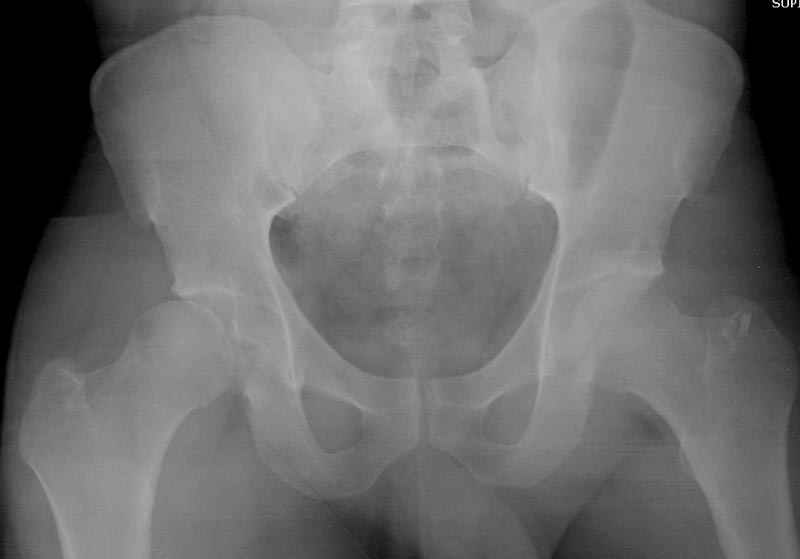

Выставлена на обсуждение (только одна проекция) рентгенограмма больного 25 лет, поступившего в приемное отделение, молодой дежурный врач сомневается в тактике лечения и спрашивает совета.

С его слов, больной стабилен,травму получил в результате автоаварии.Подскажите, что делать?Джолдас Кульджанов

5:24 Рентгенограмма таза, вызывают врача ортопеда (снимок N1), его диагноз: закрытый переломо-вывих правого тазабедренного сустава, получает добро на закрытую репозицию в приемном отделении

Кроме вывиха виден перелом задней стенки, насчет задней колонны не уверен (видна линия перелома дистальнее ацет. крыши - подвздошная проекция или СТ помогли бы прояснить ситуацию). Поэтому с такой ситуации только закрытое вправление без рефиксации фрагмента задней стенки может привести к рецидиву вывиха (с чем имел неприятность столкнуться не так давно).

На первый взгляд, бедро надо вправить, наложить вытяжение, и дообследовать - Judet views, CT вертлужной впадины, чтобы оценить дефект задней стенки. Вероятно, придется делать остеосинтез заднего края.